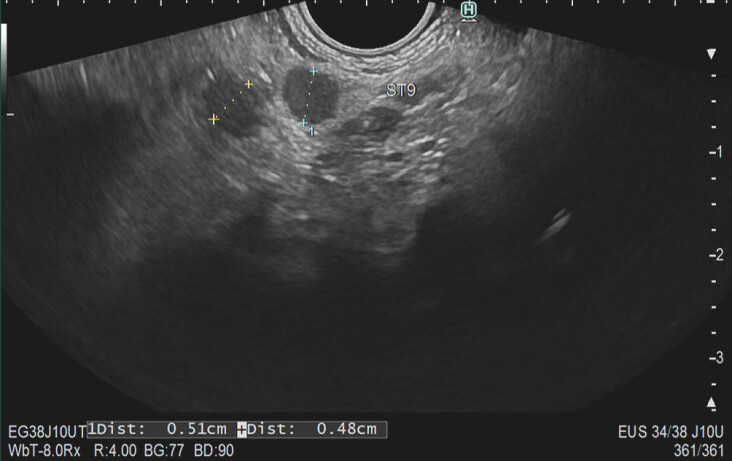

Methods: A cross-sectional survey study was conducted among 24 endosonographers. Participants reviewed 42 EUS images from iCCA and pCCA patients, classifying LNs based on six characteristics (demarcation, shape, echogenicity, homogeneity, suspiciousness, and need to retrieve tissue). Interobserver agreement was determined using Light's kappa statistics. Accuracy, sensitivity, and specificity in identifying malignant LNs were calculated.

Results: Overall kappa values indicated moderate to fair agreement on LN characteristics, with Kappa values of 0.24 for demarcation, 0.45 for shape, 0.38 for echogenicity, 0.52 for homogeneity, and 0.36 for suspiciousness. Overall accuracy of endosonographers in correctly identifying malignant LNs was 62%, with individual accuracy ranging from 44 to 75%. Sensitivity was 60% (range: 29%-90%) and specificity was 64% (range: 28%-89%).